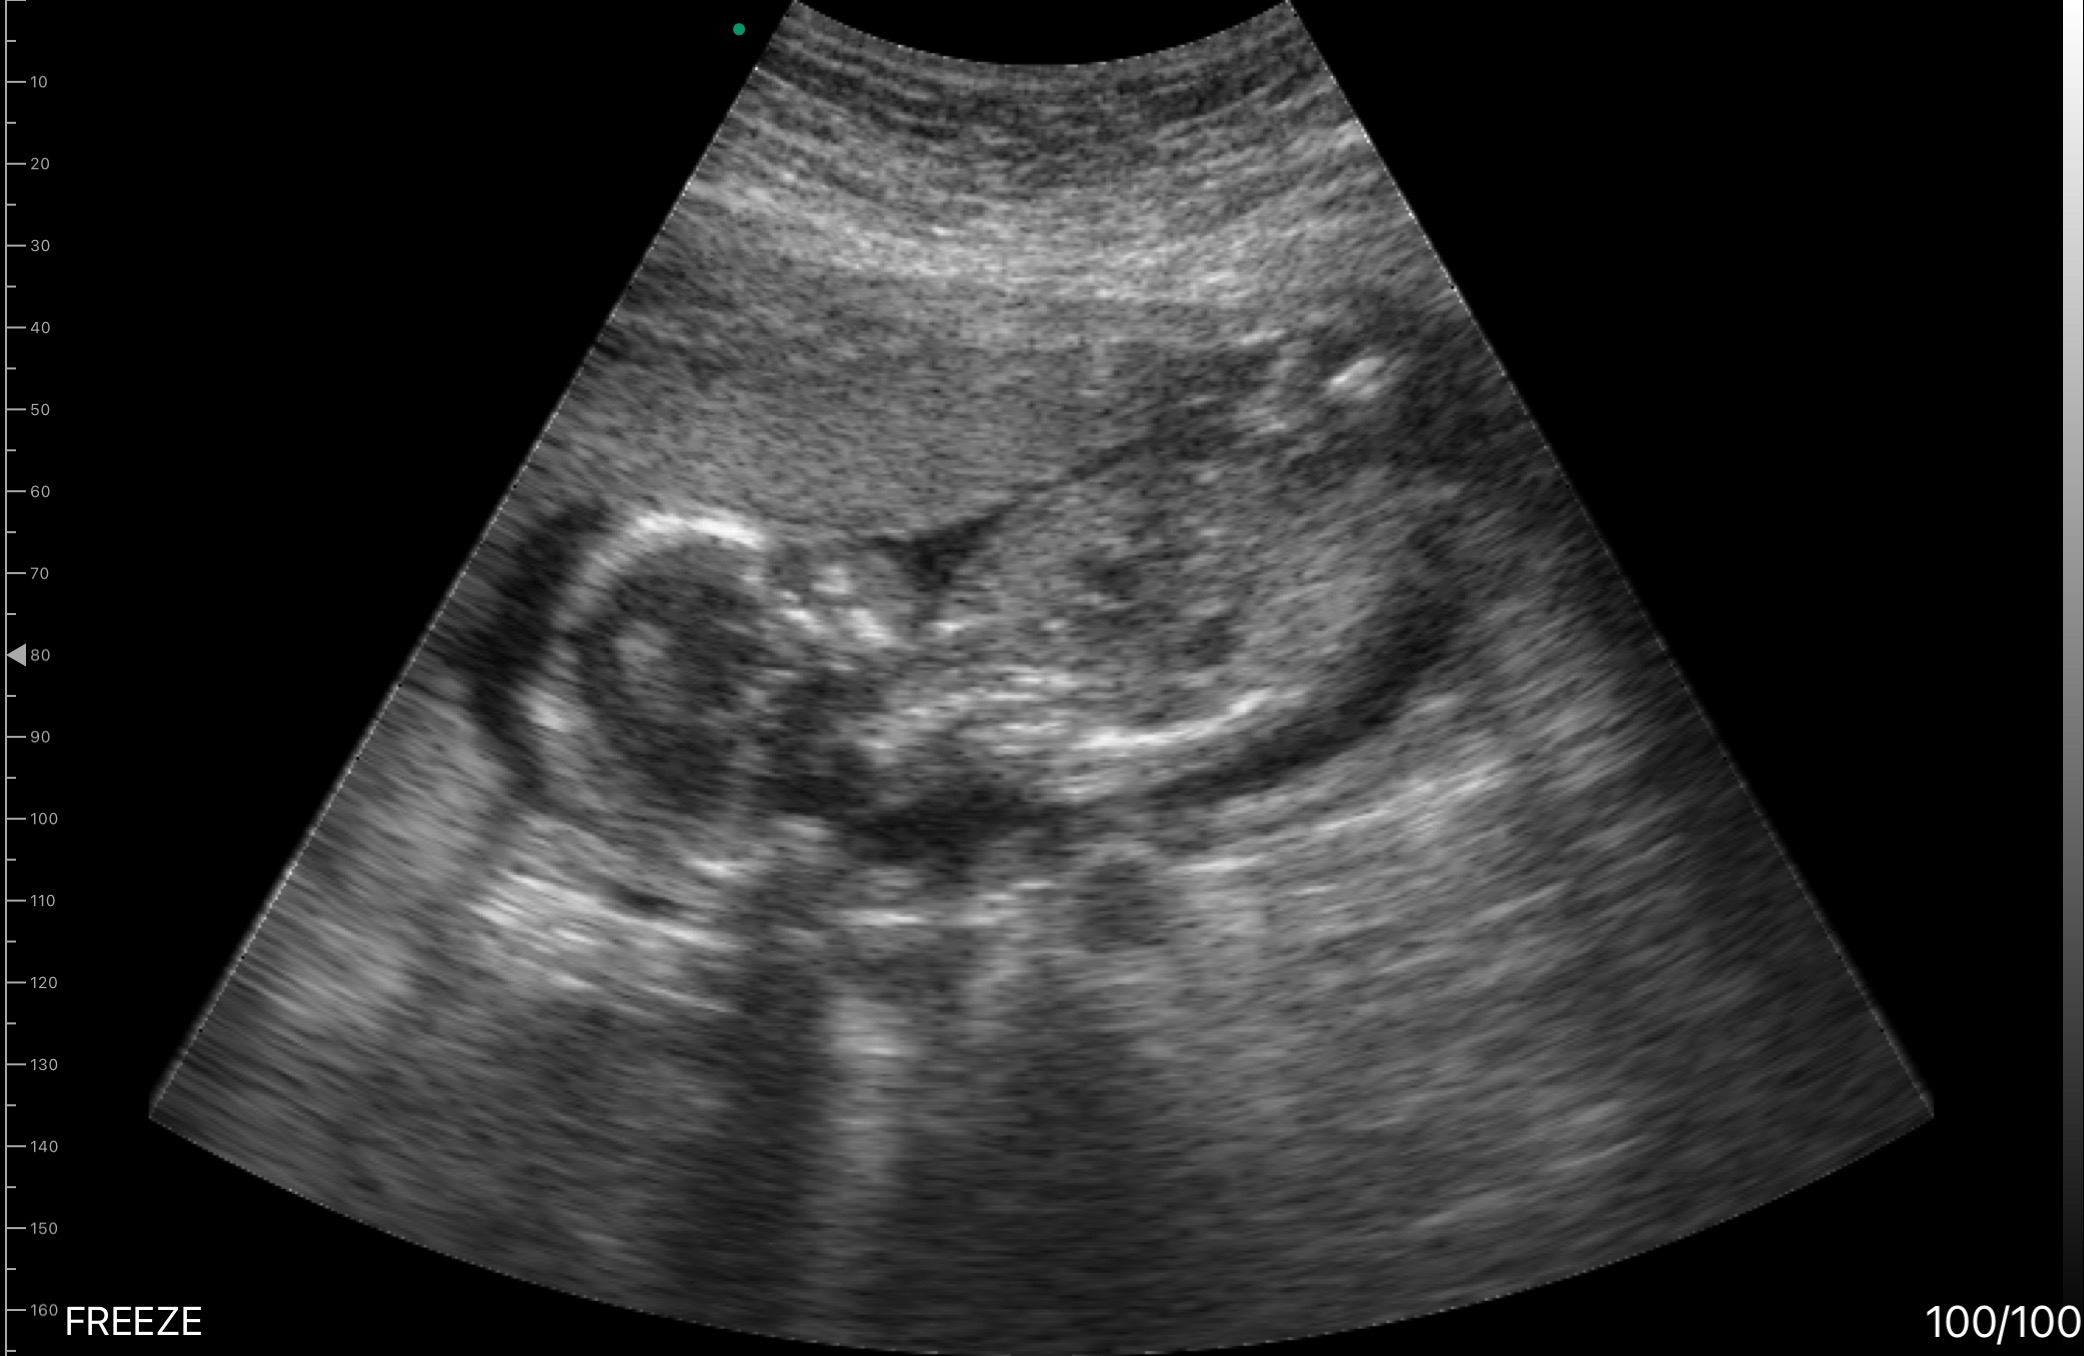

Starting at 15 weeks, I had some bleeding which took me to the ER, and I had an infection for a while. I had to go back due to bleeding continuously and was diagnosed with a Subchorionic Hemorrhage, which is bleeding between the uterine wall and the chorionic membrane surrounding the fetus, causing vaginal bleeding and cramping. Between the time of me being diagnosed to now, I've had 3-4 ER visits due to excessive bleeding and had to be put on restrictive activity, making it harder to care for my daughter Nova, who is 2.5 years old. In between one of those ER visits, we found out that my hemorrhage has gotten bigger and turned out to be a Subamniotic Hemorrhage, which is bleeding between the amniotic membrane and the fetal chorionic plate. This is a lot more serious and comes with a lot more complications such as preterm birth and other fetal issues.

This morning, my water unfortunately has broken. I am only 23 weeks and 2 days into my pregnancy journey. I have been presented with the worst-case scenario that could happen to someone in my condition. I am now living at the hospital until baby girl comes, which could be days, weeks, or months. The doctors here are trying to safely prevent and slow down labor as much as possible so our baby girl has a stronger chance at life. I am on complete bed rest, so I am unable to care for my daughter without someone with me. I thankfully have a little village to help on certain days, but there could be days Brenton will have to miss work due to no one being able to help.